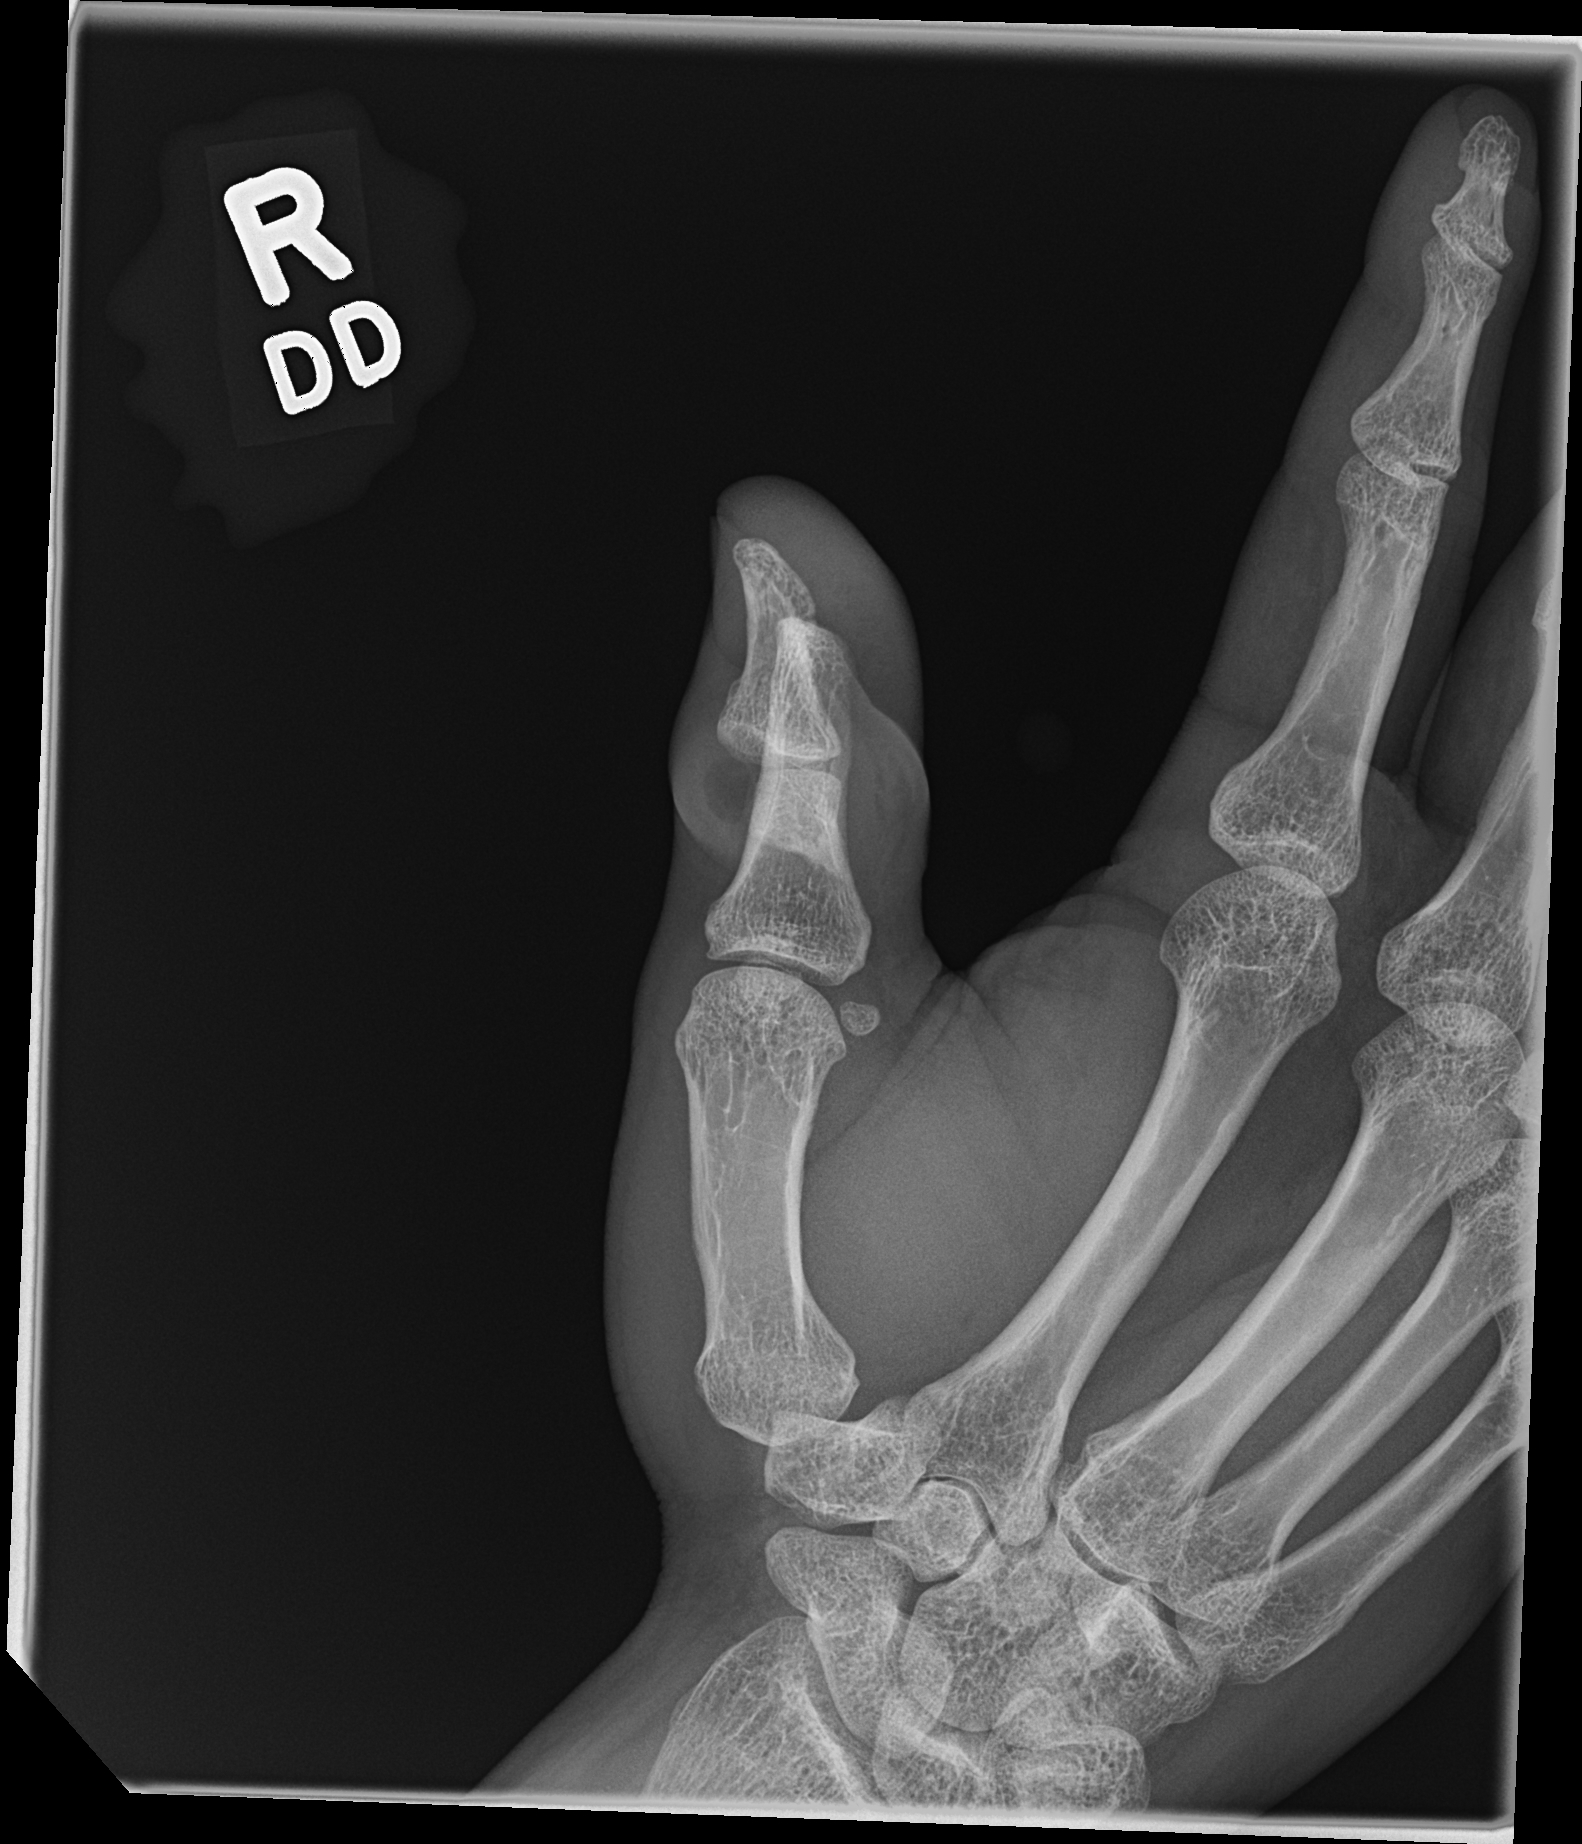

Open fractures represent high acuity injuries requiring rapid evaluation and management for optimal outcomes. In this report, we discuss a patient presenting with an open fracture of the proximal phalanx of the right thumb with interphalangeal (IP) joint dislocation. The patient reported that the injury occurred in the setting of trauma from catching a cricket ball, experiencing immediate severe pain and bleeding. Key interventions in the emergency department included rapid x-ray evaluation of the injury, administration of cefazolin and tetanus vaccine, pain control, covering the exposed bone in moist gauze, and involvement of the hand surgery team for bedside irrigation and reduction. He underwent open reduction and internal fixation of the fracture the next day. He was followed in the hand clinic and was doing well at the 12-week appointment. In summary, we report on an open fracture and dislocation of the proximal phalanx of the thumb secondary to a traumatic cricket injury. Early mobilization of the surgical team and adjunctive prophylaxis with cefazolin and updated tetanus were key measures in the emergency department for achieving optimal outcomes.